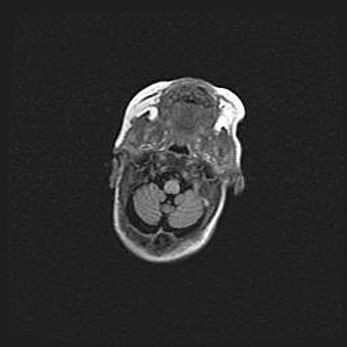

Мальформация Денди-Уокера. Киста задней черепной ямки.

Агенезия мозолистого тела.

Возраст: 2,5 месяца

Вес: 2420 г

Пол: женский

Окружность головы: 37 см

Срок гестации: 32 недели

Мальформация Денди—Уокера — редкий вид патологии ЦНС, представляющий собой врожденный порок развития каудального отдела ствола и червя мозжечка, ведущий к неполному раскрытию срединной (Мажанди) и латеральных (Лушка) апертур IV желудочка мозга. Для этогно синдрома характерна триада симптомов: гипотрофия червя мозжечка и/или полушарий мозжечка, кисты задней черепной ямки, гидроцефалия различной степени. В 70% случаев порок сочетается и с другими аномалиями головного мозга, в частности с агенезией мозолистого тела.